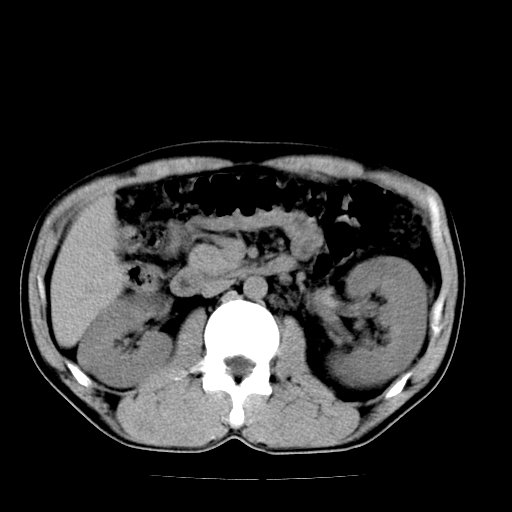

以下是引用天南地北在2007-4-30 13:36:00的发言:[br]支持慢性胰腺炎伴有假性囊肿

以下是引用andymaomao在2007-4-30 14:28:00的发言:[br]支持:1.慢性胰腺炎并假性囊肿形成可能;[br] 2.左肾形态稍增大,旋转不良。